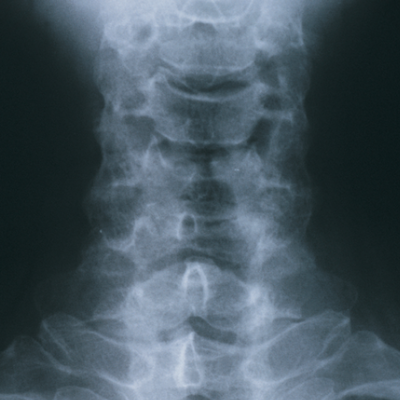

최근 목 디스크는 정말 급증하고 있는 질환중 하나입니다. 목디스크는 경추 뼈와 뼈 사이에 존재하는 추간판, 즉 디스크가 탈출함으로써 경추 신경을 자극해 통증을 유발하는 질병입니다.

정상의 목뼈는 C자형을 유지하고 있는 반면 지속적으로 잘못된 자세로 생활습관이 들다보면 목이 일자목으로 변형되고 더 악화되면 결국 거북목이 됩니다.